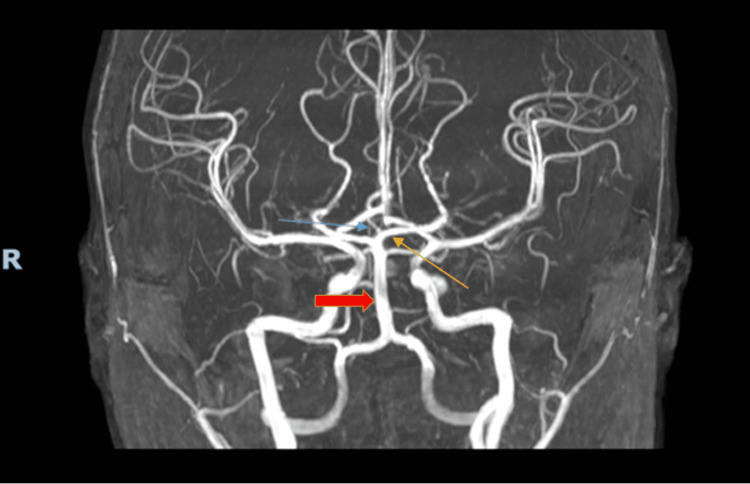

Excellent presentation by @PereraKanjana 👏🏻👏🏻 Aproach to ESUS workup ✅️ CTA is superior to MRA (prone to artifatcs) ✅️ TEE/TCD with microbubbles in the young ✅️ Prolonged cardiac monitoring - older patients #ISC26 @StrokeAHA_ASA